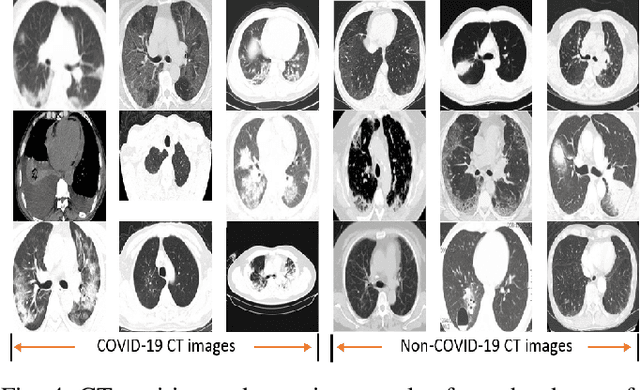

Abstract:One of the most serious global health threat is COVID-19 pandemic. The emphasis on improving diagnosis and increasing the diagnostic capability helps stopping its spread significantly. Therefore, to assist the radiologist or other medical professional to detect and identify the COVID-19 cases in the shortest possible time, we propose a computer-aided detection (CADe) system that uses the computed tomography (CT) scan images. This proposed boosted deep learning network (CLNet) is based on the implementation of Deep Learning (DL) networks as a complementary to the Compressive Learning (CL). We utilize our inception feature extraction technique in the measurement domain using CL to represent the data features into a new space with less dimensionality before accessing the Convolutional Neural Network. All original features have been contributed equally in the new space using a sensing matrix. Experiments performed on different compressed methods show promising results for COVID-19 detection. In addition, our novel weighted method based on different sensing matrices that used to capture boosted features demonstrates an improvement in the performance of the proposed method.